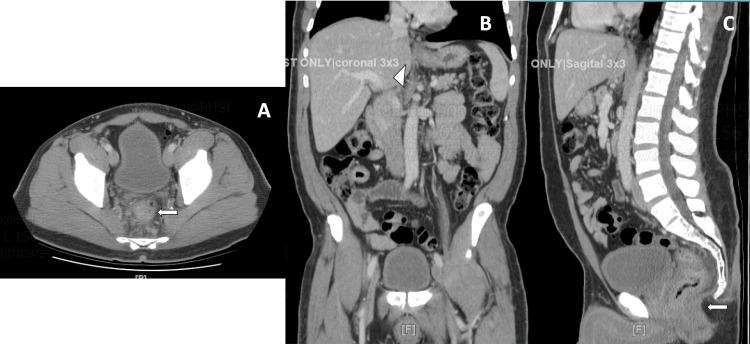

Syphilis is a sexually transmitted disease that impacts multiple organ systems and can mimic various diseases and is an extremely rare cause of proctitis in men who have sex with men and transgender females. We present a case of a 49-year-old transgender female with a medical history significant for diabetes mellitus and hyperlipidemia who presented to the emergency department with dull abdominal pain in the left upper and lower quadrants for two days. She had non-bloody, nonbilious emesis, 10-pound weight loss over 1 month, and constipation for 2 weeks. Laboratory results showed a cholestatic pattern. Computed tomography of the abdomen showed rectal wall thickening, multiple enlarged perirectal adenopathy, and mild inflammatory infiltration around the rectum suggesting superimposed proctitis. On colonoscopy, a possible rectal mass or severe proctitis with near complete obstruction was seen with initial pathology concerning for lymphoma or a rare type of colitis. The patient was empirically started on ceftriaxone and doxycycline leading to improvement in inflammation. Special stains requested were positive for Treponema pallidum confirming the diagnosis of syphilitic proctitis and highly suggestive syphilitic hepatitis. Few cases of syphilitic proctitis imitating rectal malignancy and syphilitic hepatitis have been reported. Syphilis requires exclusion as well as confirmation of spirochetes for high-risk populations with special staining. It is important to diagnose syphilis in special populations that are at high risk of contraction.

梅毒是一种性传播疾病,可影响多个器官系统,能模仿多种疾病,是男男性行为者和变性女性中直肠炎极为罕见的病因。我们报告一例49岁变性女性病例,其有糖尿病和高脂血症病史,因左上腹和左下腹钝痛两天就诊于急诊科。她有非血性、非胆汁性呕吐,1个月内体重减轻10磅,便秘2周。实验室检查结果显示胆汁淤积模式。腹部计算机断层扫描显示直肠壁增厚、多个直肠周围淋巴结肿大以及直肠周围轻度炎症浸润,提示合并直肠炎。结肠镜检查时,可见一个可能的直肠肿物或严重直肠炎伴近乎完全梗阻,初步病理检查怀疑为淋巴瘤或一种罕见类型的结肠炎。患者经验性使用头孢曲松和多西环素治疗后炎症有所改善。所要求的特殊染色显示苍白螺旋体阳性,确诊为梅毒性直肠炎,并高度提示梅毒性肝炎。很少有梅毒性直肠炎模仿直肠恶性肿瘤及梅毒性肝炎的病例报道。对于高危人群需通过特殊染色排除并确认螺旋体以诊断梅毒。在有高感染风险的特殊人群中诊断梅毒很重要。